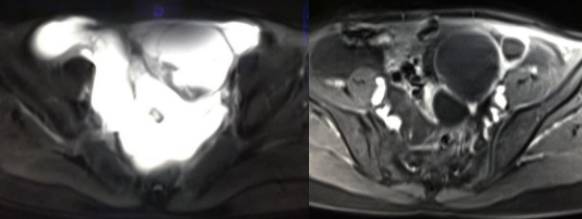

病理结果:黄体血肿

黄体血肿为正常排卵过程中,卵泡层破裂,引起出血,较多的血液潴留在卵泡或黄体腔内形成血肿。

正常黄体直径为15mm左右,以后转变为白体,并在下一个周期的卵泡期自然消退。若黄体内出血量较多,则形成黄体血肿,或称黄体内出血,出血性黄体。黄体血肿多为单侧,一般直径为40mm,偶可达100mm,黄体血肿被吸收后可导致黄体囊肿,较大的血肿破裂时可出现腹腔内出血,剧烈腹痛、少量阴道流血和腹膜刺激征,不易与宫外孕区别。

黄体血肿早期:囊内出血较多时,表现为卵巢内近圆形囊肿,囊壁厚,内壁粗糙。

黄体血肿中期:黄体血肿内血液凝固,部分吸收,囊壁变薄而,内壁光滑。

黄体血肿晚期:血液吸收后囊肿变小,转变为白体,内部回声呈实性稍高回

声,与周围卵巢组织分界不清,面靠彩超显示其周围环状血流判断,当血液完全吸收后形成黄体囊肿,囊壁变得光滑,与卵巢其他囊肿难以区分。

根据时间不同MR信号也有所不同,TIWI脂肪抑制序列可以鉴别脂肪和出血。